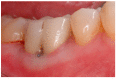

Various classification systems have been proposed to describe furcation lesions and Glickman's classification for many years seems to have been the most widely utilized in the sole clinical diagnosis with no reference to the prognostic value of the lesion itself. This article reviews the previous classification systems and proposes a new method to classify furcation lesions based on the position of the gingival margin and its relationship with the furcation area (clinically exposed/non-exposed furcation area) providing significant aid for a better understanding of furcation involvements and increases the prognostic value of treatments in the long term.